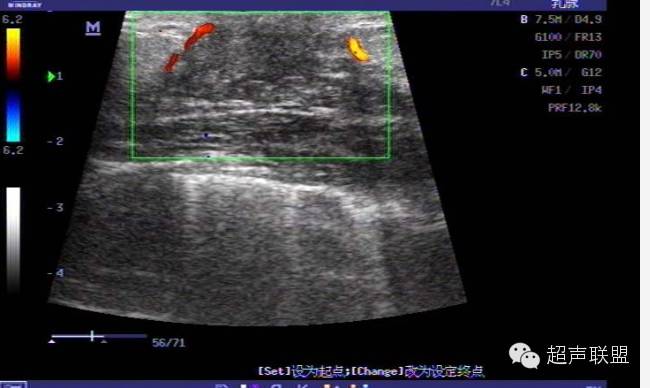

弹力图是通过在组织上施加一个微小的压力,比较挤压前后的两幅图像而获得组织的弹性特征。运用互相关法处理挤压前后获得的数据可测定各个小块组织相应于探头压力所产生的位移量。这些挤压幅度很小,通常在0.2到0.6mm之间。乳腺组织位移变化率相对于施压探头距离的变化关系,即为应变图像,进而构成了最后的弹力图。

初期研究表明,良性肿块诸如纤维增生,纤维性囊肿节点在弹力图上不可见或几乎看不见。图7呈现了典型的纤维组织增生。癌症肿瘤因比周围正常组织硬得多,在弹力图中非常明显。

癌症区在弹力图中有三种不同的模式: 非常规范的一块硬(暗色的)肿块或小结;一块硬度适中的肿块或小节点,里面具有更硬的颗粒;或是非常暗或硬的中心区域环绕着一些较弱(较亮的)周边组织。弹力图对区分乳腺纤维化与癌极为有效。纤维化在B超上表现为回声较强的区域并附带后部声学阴影,与癌症区的B超影像极为类似。然而在弹力图中,组织纤维化通常表现为一片硬度适中的均匀区并没有更硬的中心核区,相反地癌变区会突现出一块清晰而不规则的高硬度区域。

初期的工作揭示了弹力图能正确区分大多数良性与恶性肿瘤。其主要原因是恶性肿瘤比良性肿瘤更硬或更暗,而且其宽度较良性肿瘤宽。由于碳塑反应(Demoplastic),恶性肿瘤在弹力图上比在普通B超图上显得大,因为碳塑反应在恶性肿瘤四周导致了一块硬度增强的区域。